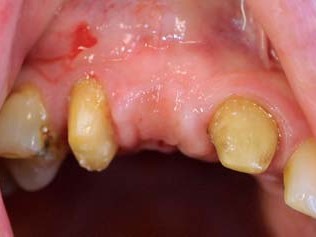

Abb 2 Klinische Ausgangssituation mit Farbwahl

Abb. 2: Klinische Ausgangssituation mit Farbwahl

Die Patientin war seit Jahren mit einer Brückenversorgung gut rehabilitiert. In der Frontzahnregion sollte die frakturierte Zirkonbrücke erneuert werden (Abb. 1 und 2). In der Molarenregion war die Entfernung des Zahnes 25 in Erwägung gezogen worden, um eine erneute Brückenversorgung durchzuführen. Dieses war aber nur mit der Präparation eines weiteren gesunden Zahnes zu erzielen. Eine Implantatversorgung wurde der Patientin nicht offeriert. Die Neuversorgung des Oberkiefers mit einer weiteren Hinzuziehung von gesunden Nachbarzähnen im Sinne einer konventionellen zahnärztlichen Lösung sah die Patientin als nicht mehr zeitgemäß an. So stellte sich die Patientin in unserer Praxis vor.